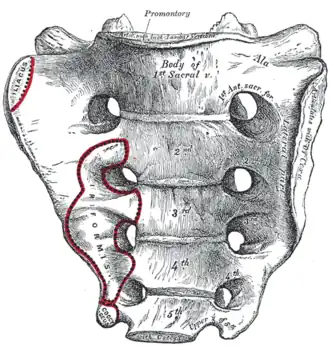

Imagem da pelve. | |

O sacro (plural: sacra ou sacrums)[1] é um osso grande e triangular localizado na base da coluna vertebral e na porção superior e posterior da cavidade pélvica, onde está inserido como uma fatia entre os dois ossos do quadril. Sua parte superior se conecta com a última vértebra lombar, e sua parte inferior com o osso da cauda ou cóccix (S1 a S5) entre 18 e 30 anos de idade.[2]